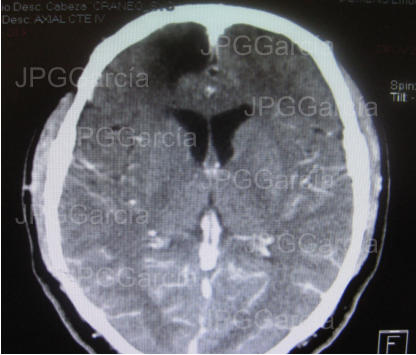

Tomografía contrastada que muestra resección de la lesión tumoral y área cicatricial post quirúrgica